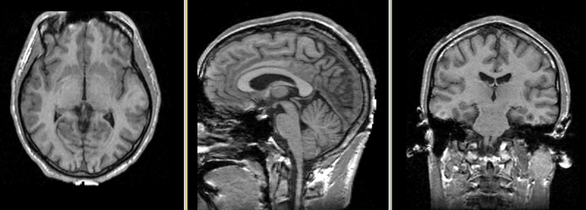

Single channel automatic segmentation of t1w-MRI brain scans into the major tissue classes (gray matter, white matter, csf). The task can only be applied to t1w brain scan showing parts of the skull and neck. The pipeline consist of the following steps:

| Template (T1) | CSF | GM | WM |